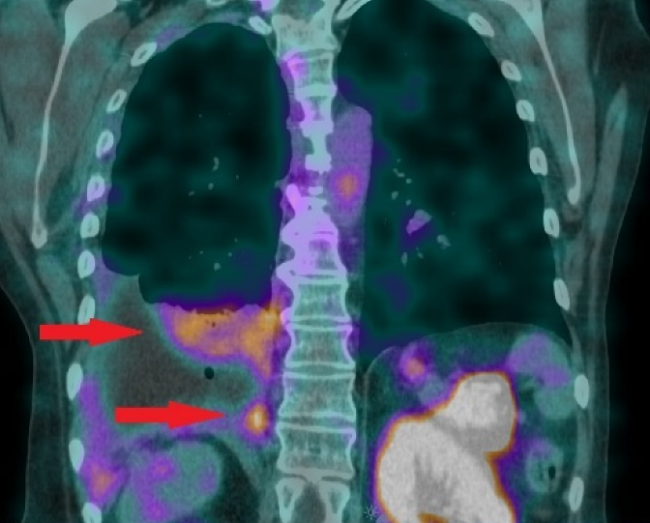

NCBJ OR POLATOM z dofinansowaniem na badania kliniczne w onkologii

Narodowe Centrum Badań Jądrowych Ośrodek Radioizotopów POLATOM otrzymał finansowanie z Agencji Badań Medycznych na realizację niekomercyjnego badania klinicznego w obszarze onkologii. Badania te dają nowe możliwości leczenia jednego z najbardziej agresywnych nowotworów piersi.

Nowoczesne nano-radiofarmaceutyki do diagnostyki i terapii

Dr Karolina Zajdel z Narodowego Centrum Badań Jądrowych otrzymała w ramach programu SONATINA Narodowego Centrum Nauki finansowanie niezwykłego projektu. Wraz z zespołem stworzy ona uniwersalne nano-radiofamaceutyki, które umożliwiały będą zarówno wykrywanie, jak i selektywne niszczenie komórek nowotworowych.